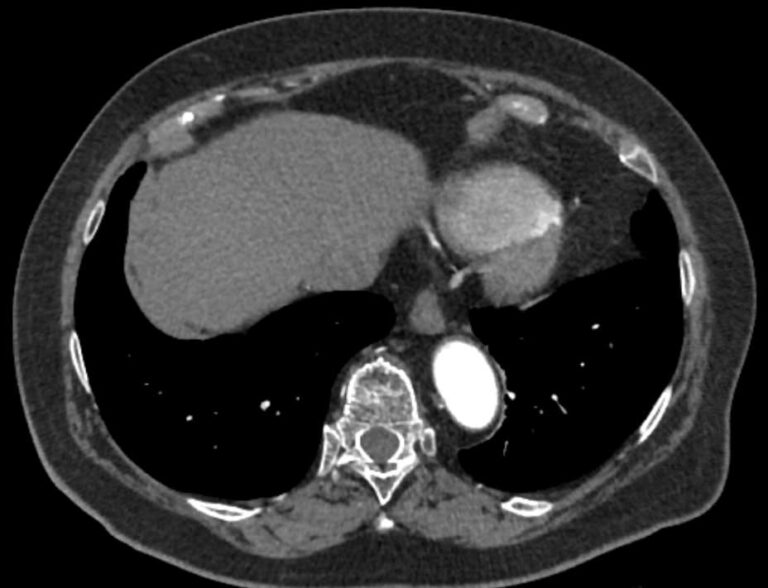

Грудная аорта делится на несколько отделов – восходящий отдел аорты, дуга аорты и нисходящий отдел. Корень аорты отходит непосредственно от левого желудочка, в его состав входят синусы Вальсальвы от которых берут начало коронарные артерии. После корня, прослеживается тубулярная часть восходящего отдела аорты, которая переходит в дугу аорты.

Дуга аорты дает начало брахиоцефальным артериям, которые питают головной мозг и верхние конечности. Затем следует нисходящий отдел аорты, распространяющийся через отверстие в диафрагме. От грудного отдела аорты отходят висцеральные артерии, кровоснабжающие органы средостения: бронхиальные, пищеводные, перикардиальные, медиастинальные артерии.

При истончении стенки аорты или ее ветвей формируется аневризматическое расширение участка сосуда, которое долгое время может никак себя не проявлять. Симптомы часто появляются при развитии осложнений – расслоения аневризмы (при разрыве внутренней оболочки сосуда и возникновения внутристеночной гематомы), разрыве аневризмы. Эти угрожающие жизни состояния можно избежать при своевременном выявлении аневризмы и проведения хирургического лечения.

Одним из информативных методов диагностики сосудистой патологии является мультиспиральная компьютерная томография грудной аорты и ее ветвей (КТ-ангиография). Метод сканирования при помощи рентгеновских лучей и цифровой обработки данных позволяет получать послойные снимки сосудов и трехмерные реконструкции сосудистой системы в мельчайших подробностях.

Для того, чтобы качественно визуализировать сосудистую систему КТ-ангиография предусматривает в обязательном порядке применение контрастного усиления. Йодсодержащее контрастное вещество вводится пациенту внутривенно и, благодаря способности контраста поглощать рентгеновские лучи, ярко контрастирует сосудистую систему на фоне окружающих тканей.

КТ-ангиография позволяет диагностировать аневризмы аорты, сосудистые аномалии развития, воспалительные изменения стенок сосудов, пристеночные тромбы, сужения просвета сосудов за счет сдавления извне близлежащими опухолевыми образованиями.